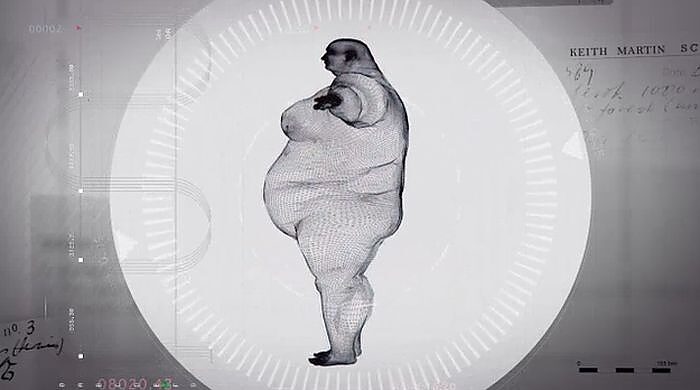

Martin, uzun yıllardır obezite hastasıDoktorlar, Martin eğer kilo vermezse 2 yıl ömrü kaldığını söylüyorlar.Martin’in Xray görüntüleri sosyal medyada büyük ilgi gördü. Çünkü Martin’in her insan gibi normal boyutta bir kemik yapısı vardıBu görüntüler zayıflamamak için kendine bahane bulan diğer kilolu insanları bilgilendirmek için dağıtılıyor.

Martin’in Xray görüntüleri sosyal medyada büyük ilgi gördü. Çünkü Martin’in her insan gibi normal boyutta bir kemik yapısı vardı